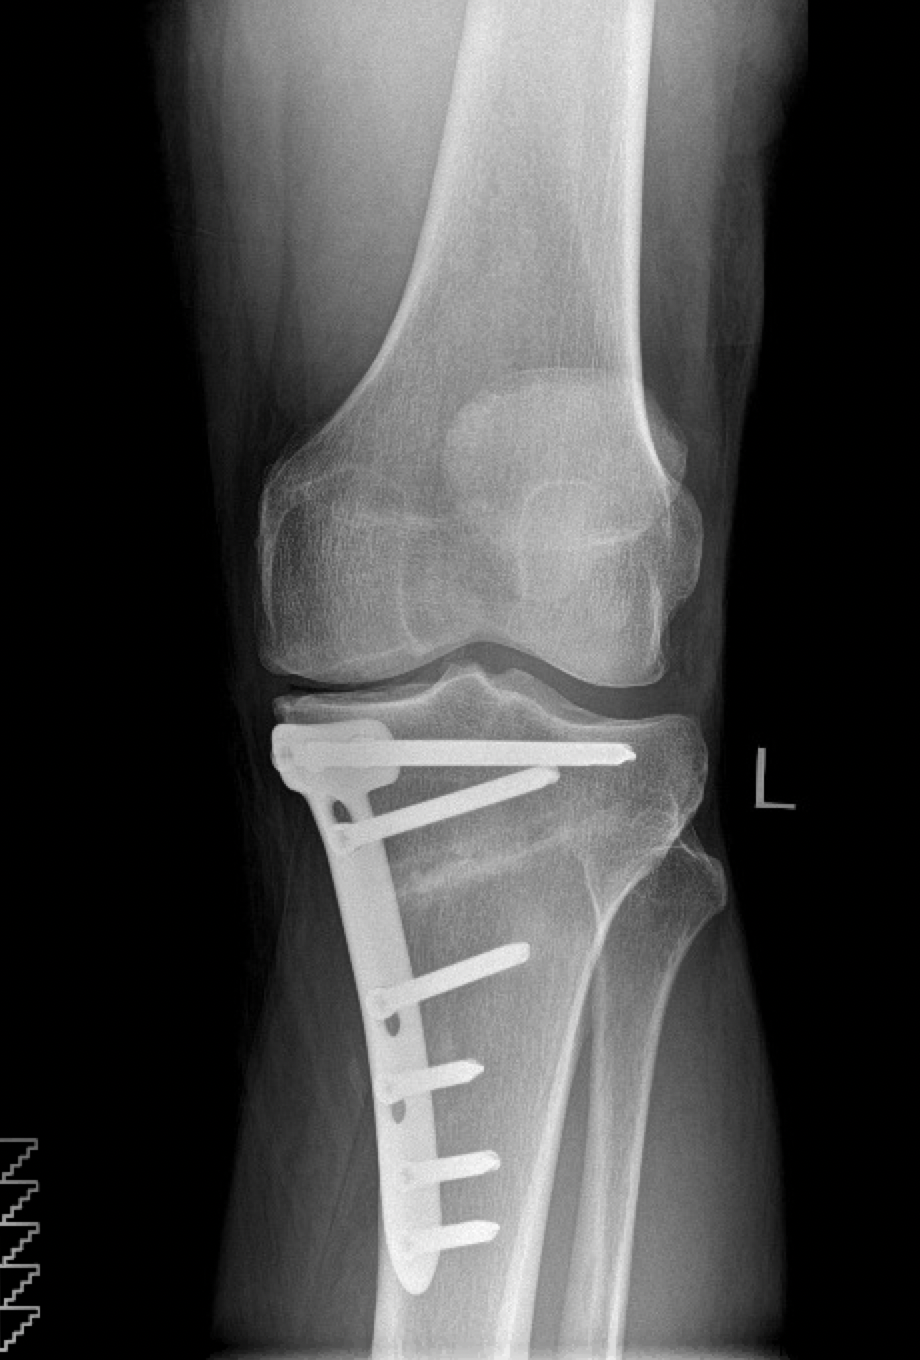

HIGH TIBIAL OSTEOTOMY

I am now more active than I have been in many years

I had High Tibial Osteotomy surgery with Mr Mihai Vioreanu in November 2016. Having osteoarthritis in my left knee left me unable to enjoy a normal active life without pain if I spent long periods walking or standing.

"Enjoying an active life"

I had High Tibial Osteotomy surgery with Mr Mihai Vioreanu in February 2015. I had been in terrible pain with my knee in 2014 following arthroscopic 'clean-out' performed in a different hospital. Mr Vioreanu was excellent during all my consultations with him. He spoke openly and plainly about the surgical procedure in layman's terms. He thoroughly discussed all the pros and cons involved. Mihai was always ready and available to assist me after surgery. I am now back to a normal lifestyle and en

"Best decision I made"

I decided to go for it and can honestly say it was one of the best decisions I made. 6 months later and I'm walking and hiking pain free, performing all manner of exercise and am working towards running/jogging.

BILATERAL HIGH TIBIAL OSTEOTOMY

"Mihai professionalism and experience is top class"

Mihai put a plan in place over three years to carry out surgery on both legs. The surgeries were a great success.